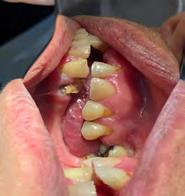

Estudios de inicio fotografías intraorales

En la Figura 3 se muesta clase III molar y canina, el overjet y overbite negativos, en la Figura 4 las líneas medias coincidentes, la mordida abierta anterior, en la Figura 5 la clase III molar y canina, overjet y overbite negativos, en la figura 6 se ven formas de los arcos ovales, el apiñamiento severo superior e inferior.